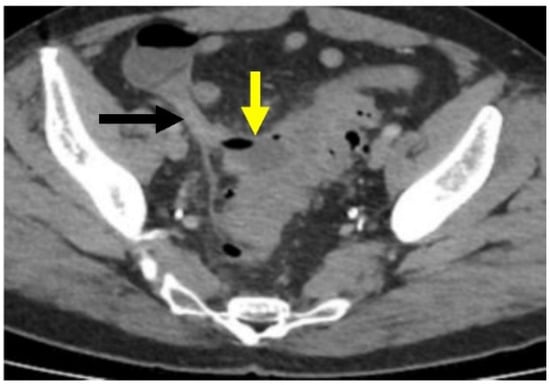

CT scanning can show complicated disease as a peridiverticular mesenteric inflammatory reaction (Hinchey Ib) or microperforation with adjacent extraluminal air (Figure 6). Contrast is also helpful to evaluate for potential abscess (Hinchey Ia or II), where rim-enhancement will be seen (Figure 5).

Figure 6.

Microperforation. Axial CT image through the pelvis with IV contrast. There is a small amount of extraluminal air (yellow arrow) along the medial wall of the sigmoid colon, without evidence for abscess. There is adjacent inflammation related to acute diverticulitis.